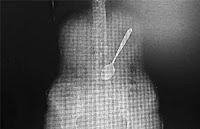

Uma mulher engoliu, sem querer, uma colher de 15 centímetros de comprimento ao comer macarrão instantâneo. Ela precisou ser levada para um hospital em Yangzhou, província de Jiangsu, na China, para extrair o objeto. Os médicos tentaram retirar a colher usando um instrumento médico longo para ‘pescá-lo’ a partir de seu estômago. Em casos semelhantes, o procedimento foi feito em apenas alguns minutos, mas, desta vez, os médicos tiveram dificuldade, devido ao posicionamento do utensílio. Felizmente, após duas horas, eles conseguiram retirar com cuidado a colher de seu estômago, sem qualquer dano interno. A mulher disse que a colher escorregou por sua garganta enquanto ela tentava, aparentemente, sugar uma porção de macarrão, que havia preparado para seu almoço. A equipe do hospital pareceu não acreditar na história da ingestão acidental da colher, acreditando que ela seria muito grande para ter passado por sua garganta. Quando questionada, Wang se recusou a entrar em detalhes sobre como exatamente a colher foi parar lá. (IBahia)